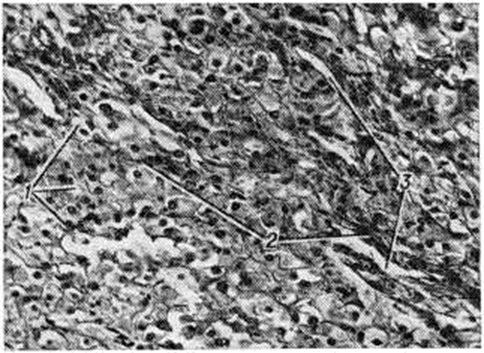

Эпителиоидный компонент в обоих типах Текома представлен большими округло-полигональными клетками, формирующими тяжи, поля и гнезда, разделенные соединительнотканными прослойками с большим количеством капилляров (рисунок).

Клеточные границы хорошо различимы, цитоплазма обильная, оксифильная, мелкозернистая с разным количеством различных по размеру вакуолей. Вакуолизация цитоплазмы этих клеток обусловлена растворением липидных включений в процессе гистологической обработки ткани. Ядра эпителиоидных клеток большей частью округлые, относительно большие, часто с чётко различимыми ядрышками. Локализация ядер и их структура нередко зависят от количества липидов в цитоплазме: чем больше число липидсодержащих включений в цитоплазме, тем ближе к периферии клетки располагается ядро и тем меньше оно по размеру и плотнее по консистенции. В эпителиоидных опухолевых клетках обнаружена очень высокая активность 3β-гидроксид-Δ5-стероид-дегидрогеназы (КФ 1.1.1.145), глюкозо-6-фосфат—дегидрогеназы (КФ 1.1.1.49), НАД и НАДФ-тетразолий-редуктазы и других ферментов, что отражает высокую функциональную активность этих клеток. Наблюдают определенную зависимость между активностью ферментов стероидогенеза и содержанием липидов в клетке: чем больше липидных включений в цитоплазме, особенно этерифицированного холестерина, тем ниже активность этих ферментов, и, наоборот, чем меньше содержание липидов, тем выше активность ферментов стероидогенеза. Для ультраструктуры клеток паренхимы Текома характерно наличие большого числа митохондрий, хорошо развитого комплекса Гольджи и разнообразие липидных включений.

Рис

Микропрепарат текомы эпителиоидно-клеточного типа: 1 — эпителиоидные клетки округлой и полигональной формы; — соединительнотканные прослойки; — капилляры; окраска гематоксилинэозином; ×400.